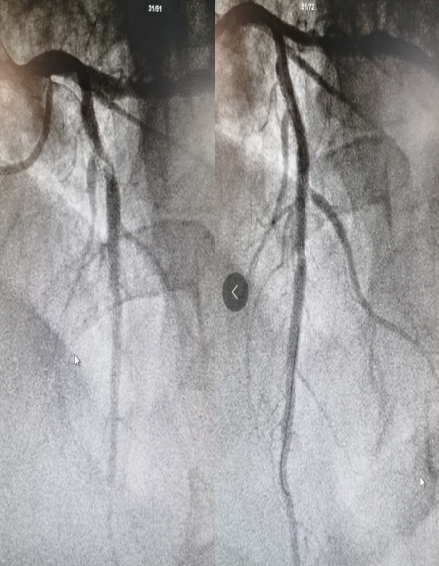

81岁男性患者,7年前因急性心肌梗死植入2枚支架,这次因“持续胸痛4小时”在当地县医院诊断为“急性前壁ST段抬高性心肌梗死”并行静脉溶栓治疗,溶栓同时联系120转入5123导航五湖四。心血管内科高江峰主任接到通知立即组织人员启动导管室,患者转入后直接行冠脉造影,冠脉造影显示:患者前降支原支架内98%狭窄伴血栓。支架内再狭窄,为药物球囊扩张的绝对适应症。当日正赶上药物球囊降价的当口,该患者成为5123导航五湖四首位享受集采优惠价药物球囊的患者,使用的药物球囊由原来的单个28000元降价到6297.70元。

药物球囊治疗前后对比图